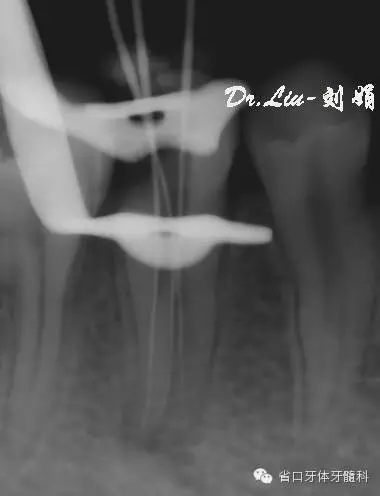

拍攝CBCT顯示為45根管下段分為3條根管

圖2/3:拍攝CBCT顯示45為3個根管。